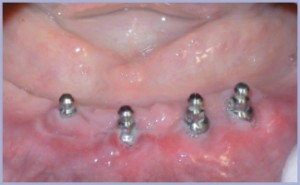

L’esame ortopanoramico (fig. 17) metteva in evidenza una discreta quantità di osso disponibile nel settore mascellare anteriore per cui si decideva per l’inserimento di 6 impianti. Lo scarso spessore vestibolo orale dell’osso residuo richiedeva tecniche espansive per l’inserimento degli impianti (fig. 18), tutti di diametro 3,3 mm. L’esame ortopanoramico (fig. 19), eseguito a 6 mesi dal posizionamento implantare, metteva in evidenza l’integrazione degli impianti confermata clinicamente al momento della seconda fase chirurgica (figg. 20, 21).

Al momento della consegna i tessuti molli presentavano un buon grado di maturazione nonostante fossero trascorse solo due settimane dalla seconda fase chirurgica (figg. 26, 27, 28).